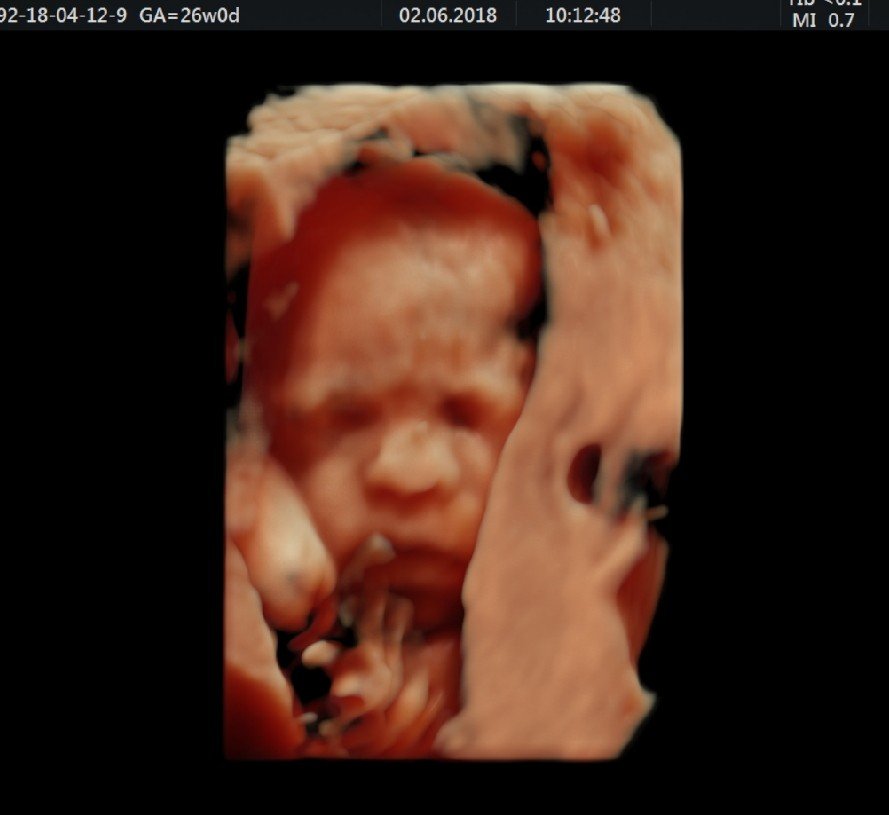

Hej dziewczyny ja dzisiaj byłam na wizycie prywatnej usg , chciałam powiedzieć że nasza Natalia rozwija się prawidłowo waży około 850g dzisiaj skończyła. 26 tygodni . Wymiary w normie . Za 4 tygodnie będę miała szczegółowe badanie takie przed ostatnie i jeszcze trochę i rodzimy dziewczyny od jutra zaczynam 27 tydzień . Jeszcze tylko 13 [emoji307] [emoji307] [emoji307]

A tutaj moja kruszynka

A tutaj moja kruszynka Zobacz załącznik 863125